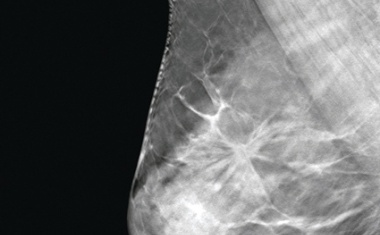

Brustbiopsie

Whitepaper